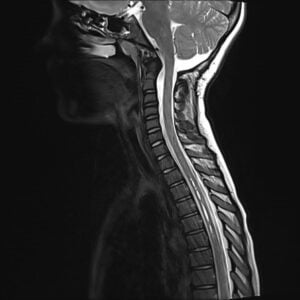

Chiari malformation (CIM) presents an interesting pathology, affecting both children and adults. It is described as a downward displacement of the cerebellar tonsils through the foramen magnum (Fig 1). This downward displacement of the cerebellar tonsils (more than 5-7mm below the foramen magnum) is the primary cause of signs and symptoms observed. This herniation can be a result of congenital or acquired malformations. There are several theories yet to be proven behind the development of congenital CIM. These include aetiologies such as small posterior fossa, hydrodynamic insults, hindbrain dysgenesis, underdevelopment of the basiocciput, lack of ventricular distention, and genetic causes [1]. Aetiology for acquired CIM may include trauma, craniosynostosis or intracranial mass lesions just to name a few [2].

Fig 1. MRI T2 sagittal cervical spine. Downward displacement of the cerebellar tonsils.